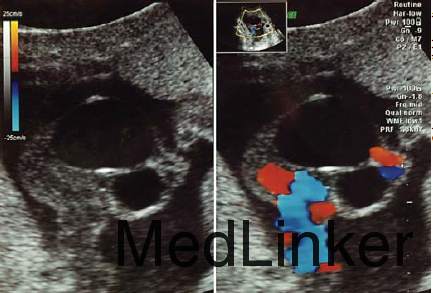

29岁女性,G2P1,孕20周因超声提示脐带囊肿就诊 既往史、妊娠史和特殊药物史无特殊

超声提示单活胎和正常羊水量,可见两个脐带囊肿,分别为21*23mm和11*15mm 无血流信号在囊肿里或囊肿周围 无其他畸形可见 孕25周超声提示两个囊肿在增大,分别是30*16mm和17*17mm 胎儿超声提示胎儿腹内脐静脉轻微扩张 孕28周,囊肿附近脐带出现水肿